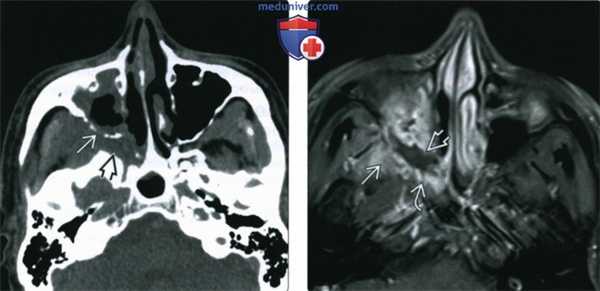

(Слева) При аксиальной КТ без КУ у пациента с диабетом и мукормикозом (ОИГРС) определяется циркулярное поражение правой верхнечелюстной пазухи с выраженными эрозиями задней стенки и замещением жировой клетчатки ретроантральной области и крылонебной ямки мягкотканным компонентом.

(Справа) При аксиальной МРТ Т1 С+ FS визуализируются фокальные неконтрастирующи-еся зоны в слизистой оболочке верхнечелюстной пазухи, соотносящиеся с некротическим струпом, жировая клетчатка ретро-антральной области и крылонебной ямки замещена мягкотканный компонентом.

(Слева) На аксиальной КТ с КУ у пациента с инвазивным мукормикозом левой верхнечелюстной и решетчатой пазухи определяется тромбоз кавернозного синуса и кавернозного сегмента внутренней сонной артерии (ВСА) слева. Обратите внимание, что правая ВСА заполняется контрастом.

(Справа) На аксиальной MPT (Т1 ВИ С+ FS) у этого же пациента определяется распространенное поражение левого кавернозного синуса, а также окклюзия интракраниального сегмента ВСА, обусловленная инвазивной грибковой инфекцией левого кавернозного синуса.